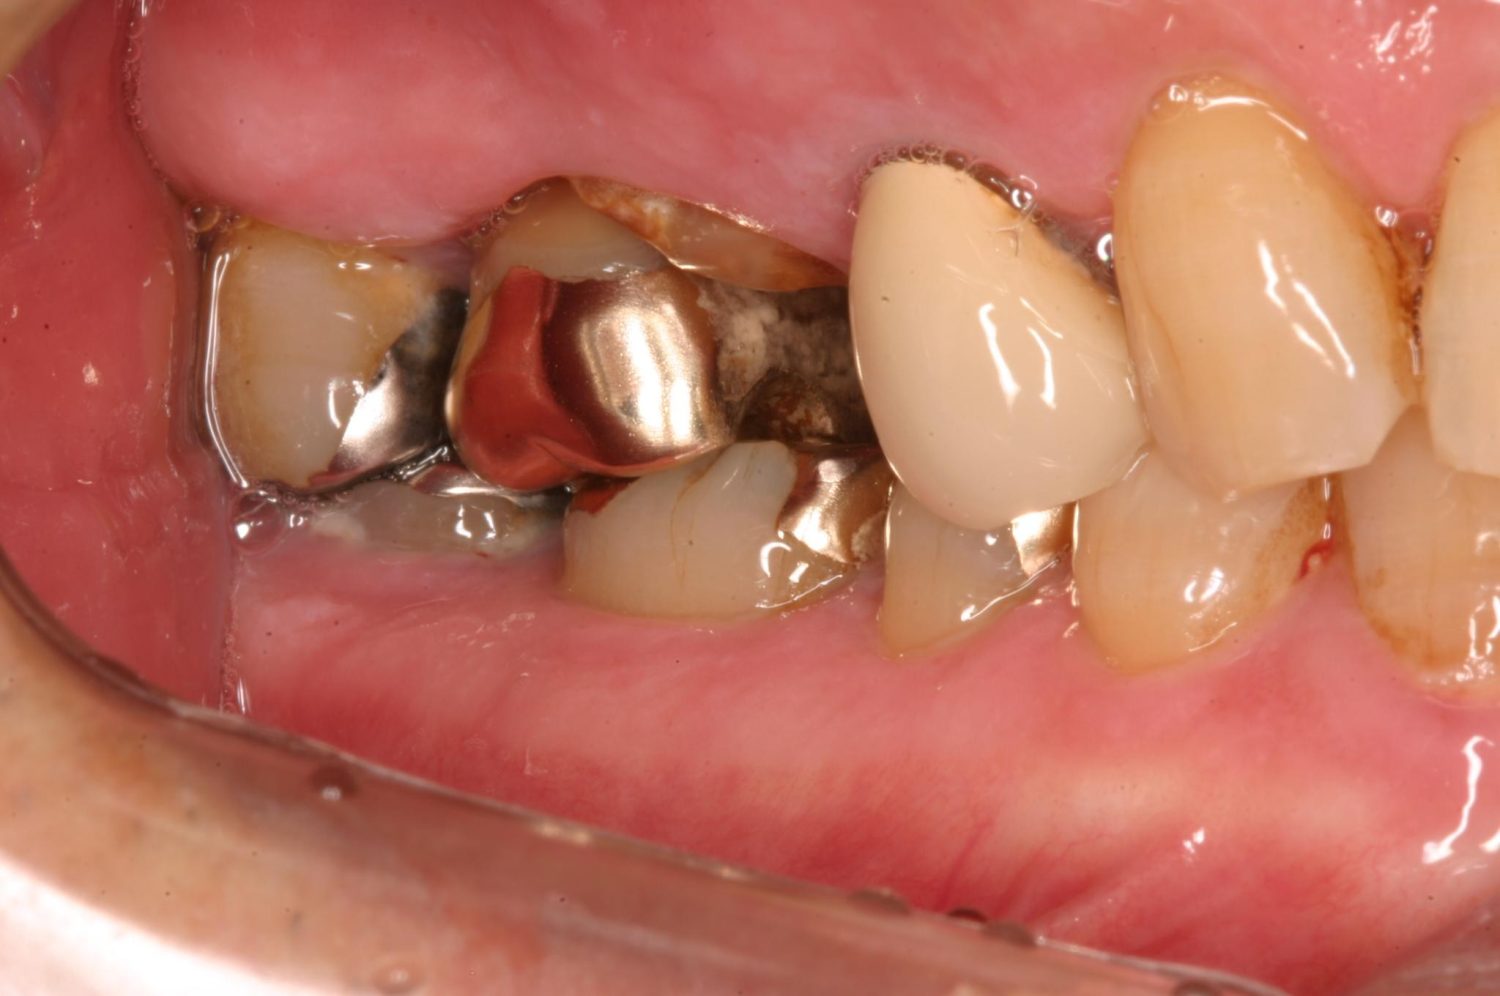

インプラント治療の症例紹介③

Before

After

主訴

むし歯の治療

治療内容

保存不可能な歯の抜歯

下顎にインプラント埋入し咬合再構成

治療費

2,688,400円(税込)

治療期間

14か月

治療回数

21回

想定されたリスク

※上部構造の形態が複雑になるため清掃が難しくなる。インプラント周囲炎の恐れがありました。

多数歯う蝕および多数歯欠損による咬合崩壊、保存不可能な歯の抜歯により上下無歯顎に。下顎に6本インプラント埋入する事で咬合再構成を行った。